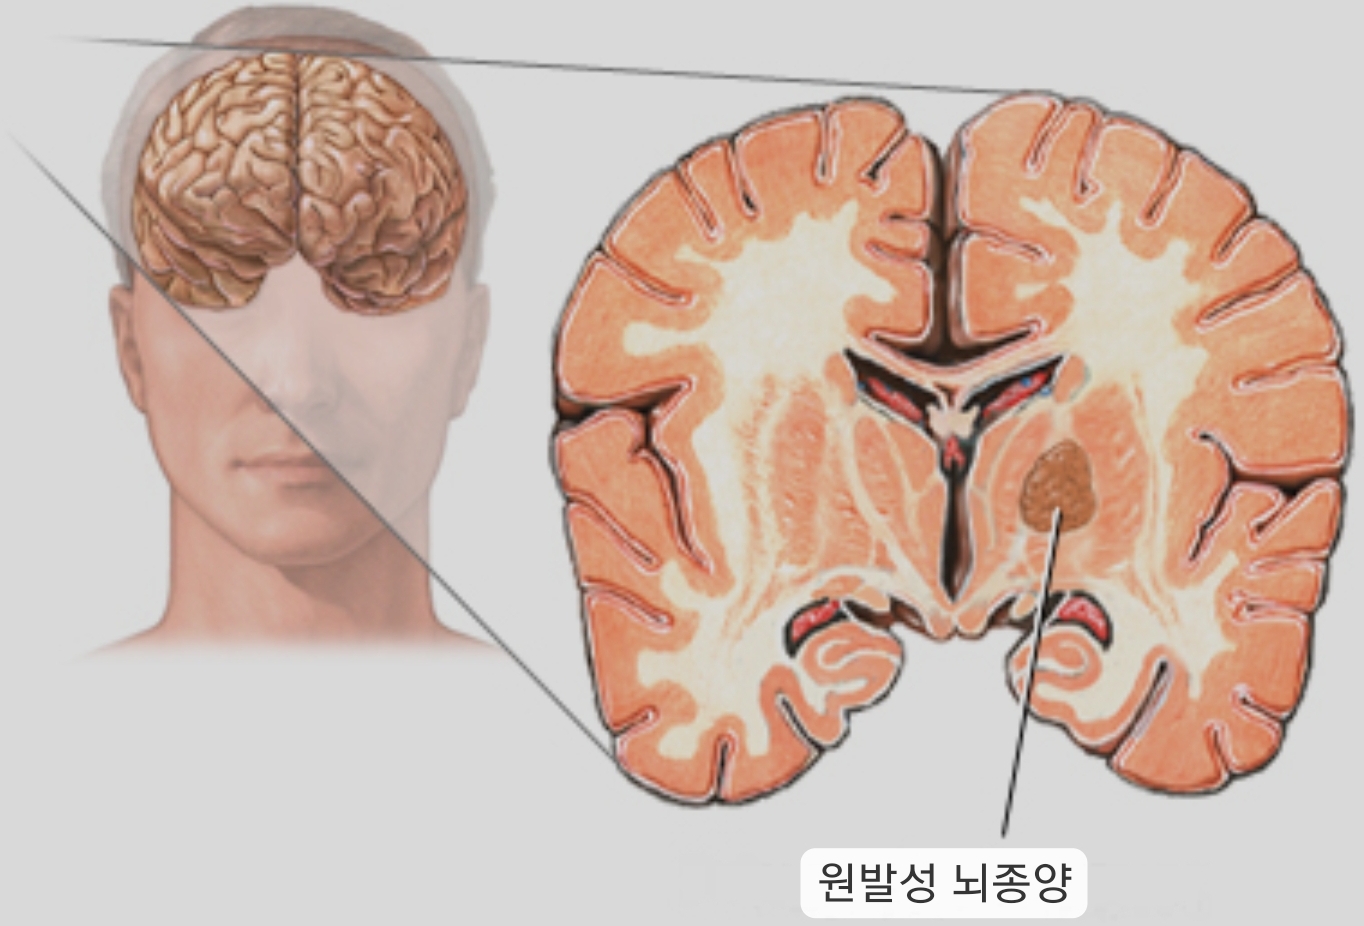

뇌종양은 뇌에서 발생하는 악성 종양으로, 뇌의 기능을 손상시켜 다양한 증상을 유발합니다.

뇌종양은 뇌의 어느 부위에서나 발생할 수 있지만, 가장 흔한 위치는 대뇌, 소뇌, 뇌하수체입니다. 뇌종양은 뇌의 정상세포가 돌연변이를 일으켜 발생합니다. 뇌종양의 원인은 아직 완전히 밝혀지지 않았지만, 유전, 방사선, 바이러스 감염 등이 위험요인으로 알려져 있습니다.